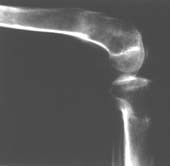

К сожалению, подобное осложнение "нет-нет да и возникает" при удлинении, коррекции деформации голени. В англоязычной литературе оно описано как "patella baja". Один из вариантов лечения - проксимальное перемещение надколенника приемами чрескостного остеосинтеза.